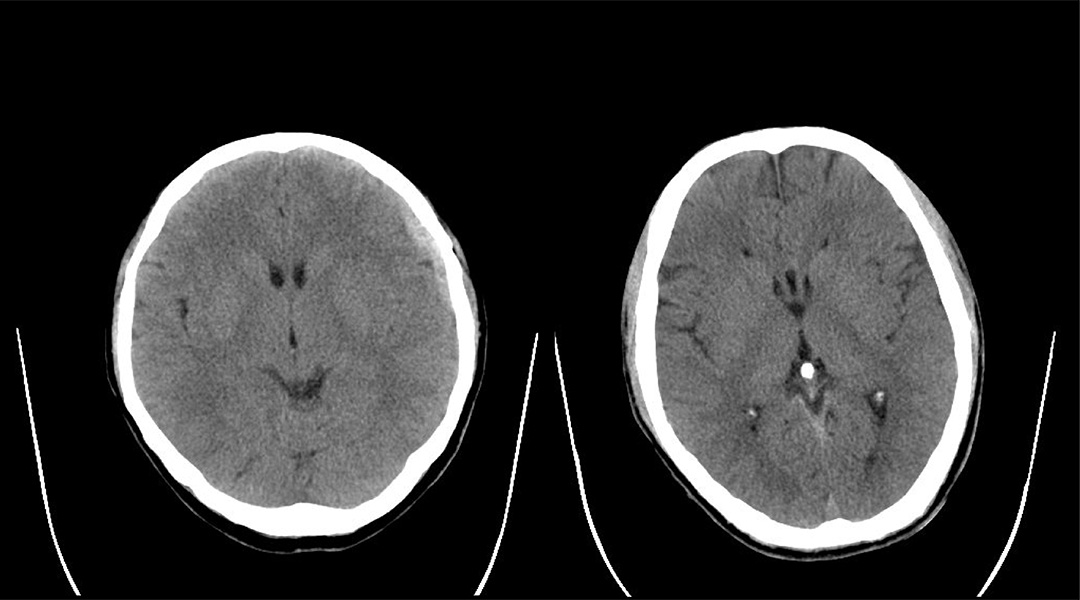

▲皓月CT超低图像噪声样片